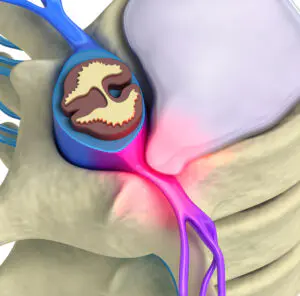

Douleurs neurologiques

Des sensations douloureuses comme des brûlures, picotements ou fourmillements. On peut les retrouver dans des sciatiques ou des maux de tête.